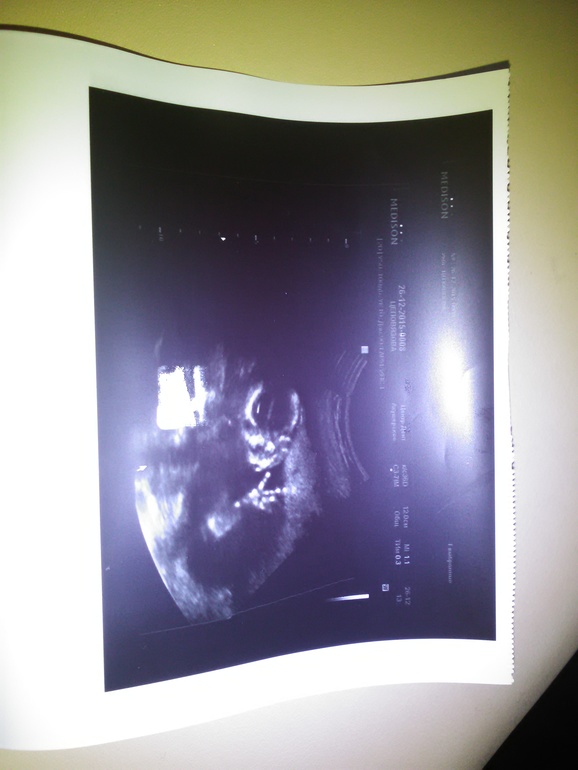

У нас в пузике живёт девчулька!

Вчера в тайне от мужа сходила на УЗИ. Сначала врач с серьёзным лицом делала измерения, потом спросила пол желаете узнать? Конечно!!!!!! Я для этого и пришла!!!! У нас девочка! Маленькая девчулька! Крошечка! Наше счастье! Показала ручки, ножки, головку. Малышка активно двигается, пальчики растопыривает, в кулачки сжимает, потом немного застеснялась, прикрыта писю рукой))) ножками болтала, скрещала ножки. Маленькая кнопочка 127 мм, примерно 130 гр. Расти наше сокровище! Папочке под елочку положу подарочек, куплю что-нибудь девчачье и снимок. Самый лучший подарочек на Новый Год!